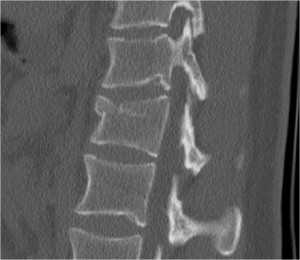

(Слева) КТ, сагиттальный срез: взрывной перелом тела L1 позвонка со смещением задней покровной пластинки в спинномозговой канал. Линия перелома продолжается на заднюю сосудистую бороздку. Нормальная сосудистая бороздка отличается от перелома ровными контурами и характерной локализацией.

(Справа) На фронтальном КТ-срезе этого же пациента виден вертикальный перелом межсуставной части дуги. Это характерное для компрессионного механизма травмы повреждение, отличающееся от горизонтального перелома задних элементов при флексионно-дистракционных повреждениях.